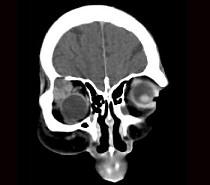

泪腺肿瘤(如图)使眼球 ( )A、向颞上方移位B、向鼻下方移位C、向上方移位D、向颞下方移位E、呈轴性前突

问题 泪腺肿瘤(如图)使眼球 ( )

选项 A、向颞上方移位 B、向鼻下方移位 C、向上方移位 D、向颞下方移位 E、呈轴性前突

答案 B